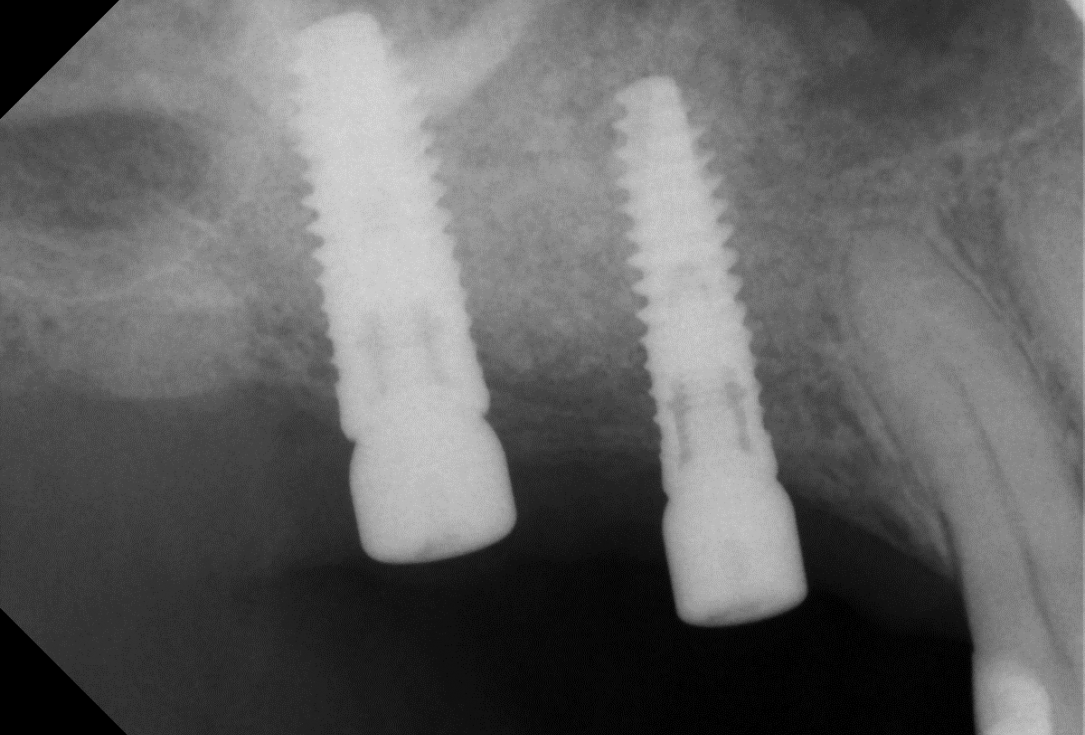

11/14 - OPG control of implant insertion

Two-stage sinus lift with maxresorb® & collprotect® - Dr. S. Kistler